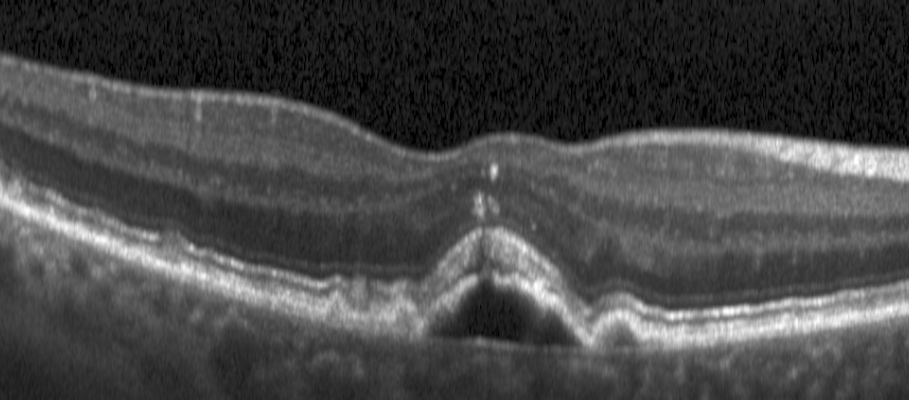

Optical Coherence Tomography (OCT) is the gold standard imaging modality for the monitoring of retinal pathologies and the management of patients with eye diseases. OCT provides clinicians with a detailed cross-sectional depiction of the retina, facilitating the assessment of diverse imaging biomarkers, notably the thickness of the retinal layers and volumes of retinal fluid compartment. These are crucial indicators for identifying and monitoring retinal diseases and guiding the treatment of pathologies such as diabetic macular edema (DME) and age-related macular degeneration (AMD), both prominent causes of global vision impairment [1]. In particular, the manifestations of AMD in the eye include, among others, intraretinal cystoid fluid (IRF), subretinal fluid (SRF), subretinal hyperreflective material (SHRM), and pigment epithelial detachment (PED) [2, 3].

Large amount of data accrued during routine clinical practice, in conjunction with the demanding clinical workflow, makes manual quantification of retinal biomarkers unfeasible in clinical practice. To combat this, automated retinal biomarker segmentation techniques have been developed, along with the commercialization and widespread adoption of OCT technology [4]. At the same time, the large variability of pathological manifestations, their effect on the signal, as well as the nature of OCT imaging, characterized by factors such as speckle noise, intensity fluctuations, and shadowing induced by biological tissues, presents a challenging task for the segmentation of retinal layers.

Recent advancements in retinal biomarker segmentation algorithms frequently rely on supervised deep learning methodologies, necessitating extensive training datasets annotated with meticulous precision[5]. However, the acquisition of high-fidelity manual annotations for pathological scenarios entails a multifaceted, labor-intensive, and resource-demanding process. Therefore, automated solutions must leverage prior anatomical knowledge. Specifically, while retinal layers maintain a consistent relative position and lesions appear in well-defined locations, the presence of lesions critically distorts layer morphology. This creates a complex bidirectional influence: layer anatomy constrains plausible lesion locations, while lesions, in turn, deform the layers. Accurately modeling this intricate relationship, especially while ensuring topological consistency, is a major challenge not fully addressed by methods treating these segmentations independently or sequentially[6, 5, 7, 8, 9, 10].